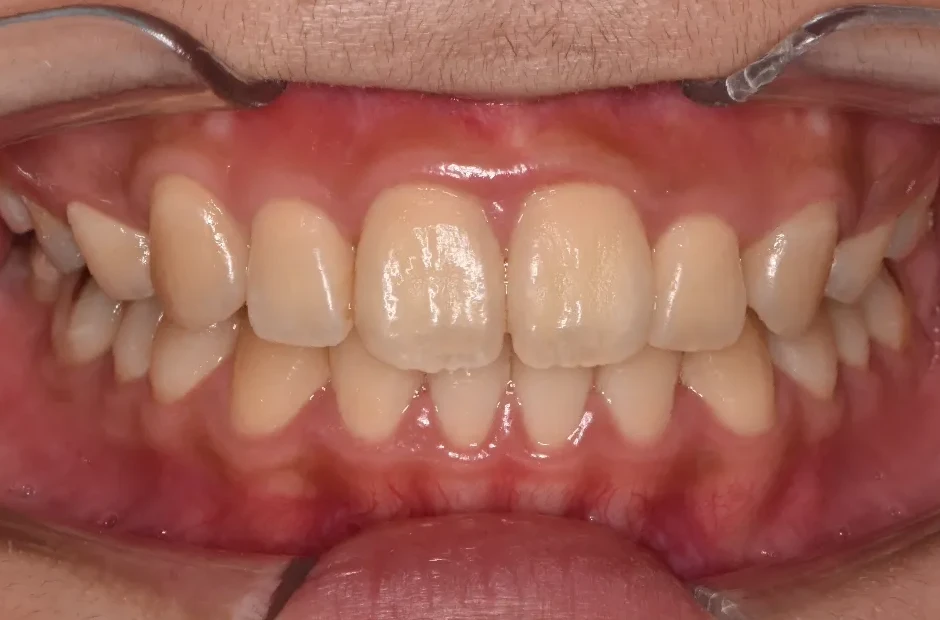

叢生

| 診断名・主訴 | 叢生 |

|---|---|

| 年齢・性別 | 43歳・女性 |

| 治療期間・回数 | 2年7か月 27回 |

| 治療に用いた主な装置 | 舌側矯正 |

| 抜歯部位 | 両顎4,4 |

| 治療費 | 100万円(税抜) |

| リスク・副作用 | 装置による違和感・疼痛・歯肉退縮・歯根吸収・虫歯のリスクなど |

治療後